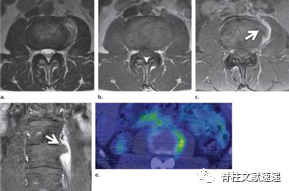

图注:背侧硬膜外椎间盘突出

图注:术前诊断倾向于硬膜外脓肿,术中见病灶呈致密纤维状,组织病理学检查显示纤维软骨盘伴反应性改变。

在MR轴位T2加权图像上可有“鹰嘴”征。典型的慢性症状;马尾综合征常见;在颈部和胸部,Brown-Séquard综合征或严重脊髓病的发病率很高。

图注:硬膜内腰椎间盘突出

图注:42岁男性,有L4/5椎间盘切除手术史,出现急性马尾综合征。术中见硬脑膜上有小开口,硬膜内部分钙化椎间盘组织。